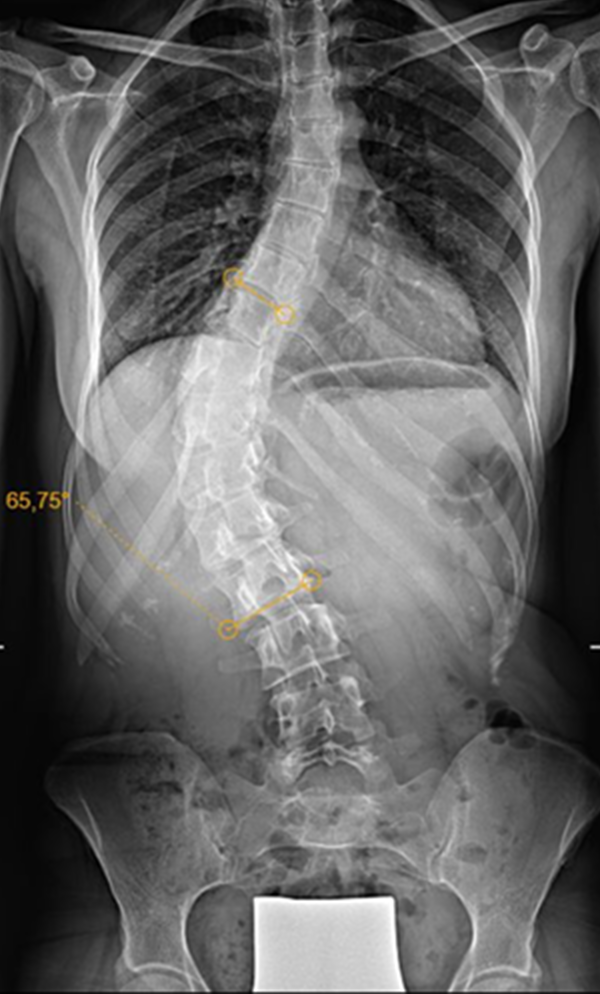

Gallery : Before - After